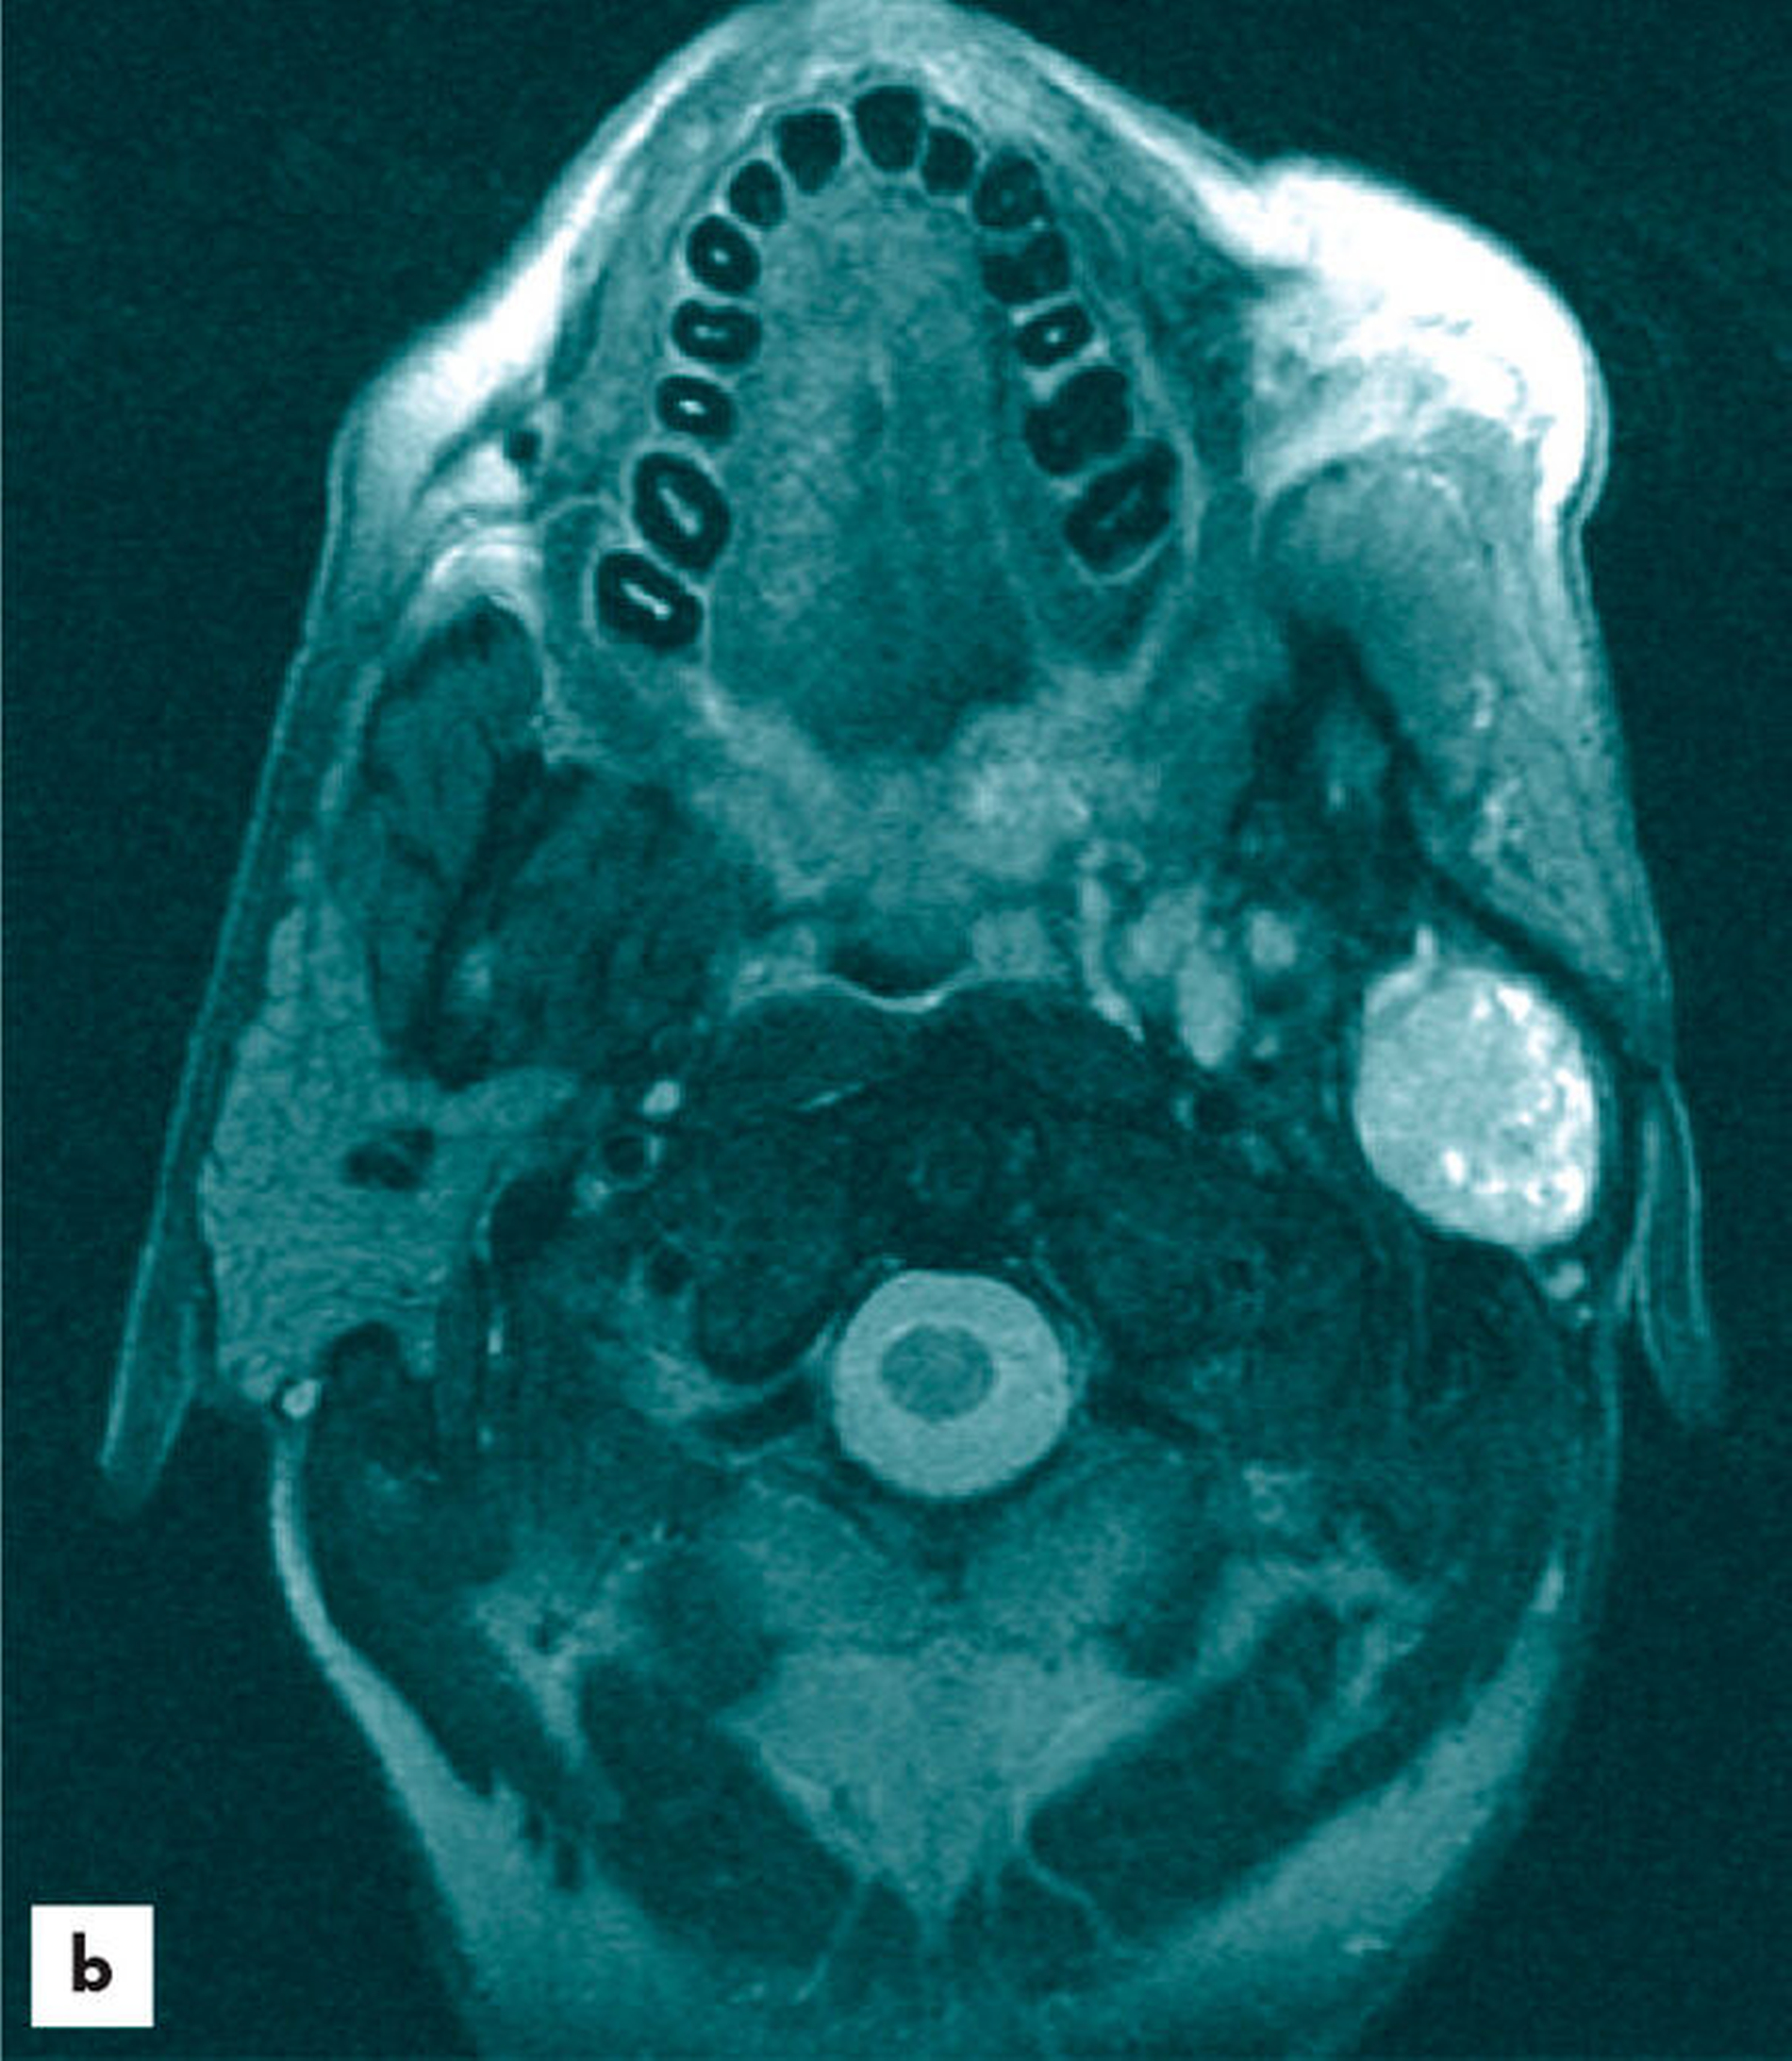

Sonografisch zeigte sich eine gut begrenzte, homogene, hyposonore Raumforderung ohne Nachweis auf eine Hypervaskularisation. Sonomorphologisch bestand damit der Verdacht auf einen gutartigen Speicheldrüsentumor. Zur weiteren Abklärung wurde eine Magnetresonanztomografie durchgeführt. Hierin stellte sich ein circa 4 cm x 3 cm großer, gut abgrenzbarer Tumor unterhalb des linken Ohres dar. Der Tumor zeigte eine Kontrastmittelaufnahme mit homogener Verteilung (Abbildung 2). Auffällige Lymphknoten kamen nicht zur Darstellung. Medial der Unterkieferrekonstruktion zeigte sich ein Parotisrest, der in Verbindung zu der Raumforderung stand. Bildmorphologisch entsprach der Befund einem monomorphen Adenom.